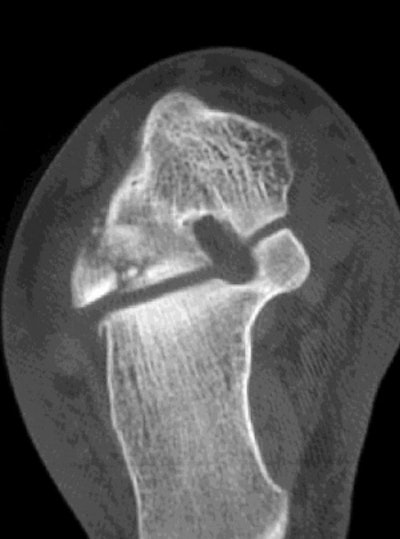

![]() |

| Coronal reconstruction CT image demonstrates extension of the fracture of the lateral process of the talus into the inferior talofibular joint. |